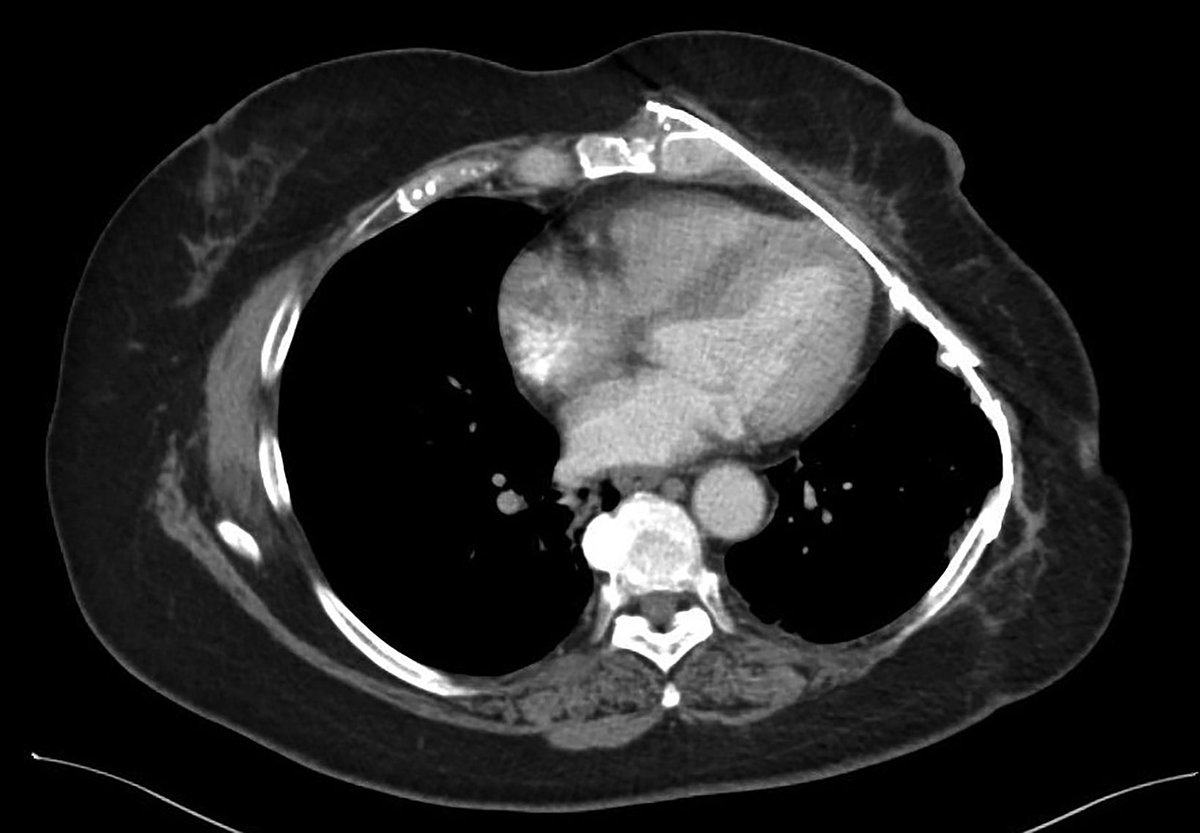

Case Study: Aggressive Multimodality Therapy for Treatment of a Locally Advanced Radiation-Related Chest Wall Sarcoma 🔗 ow.ly/UnzA50XiPaa #RadOnc #RadOncEd #CaseStudy #RadiationOncology

Applied_RadOnc's tweet image. Case Study: Aggressive Multimodality Therapy for Treatment of a Locally Advanced Radiation-Related Chest Wall Sarcoma